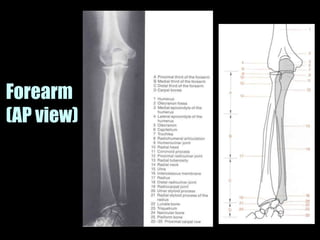

This document provides an overview of normal musculoskeletal imaging. It discusses basic x-ray concepts and densities. It then reviews normal anatomy as seen on x-rays of the skull, spine, pelvis, chest, and extremities. Key anatomical structures are labeled on example x-rays for the shoulder, hip, knee, and foot. Quizzes are included to test recognition of anatomical structures and patient age based on x-rays.